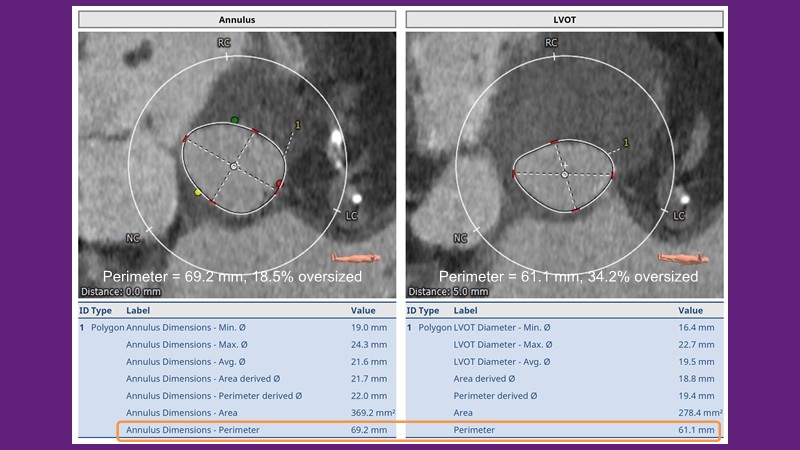

Don’t miss this PCR Tokyo Valves 2025 session replay, where leading experts share key techniques for simplifying and optimising TAVI procedures with the Evolut device. This session covers essential insights into safely performing procedures on patients with various anatomical types using the self-expandable valve, while emphasising the importance of long-term patient care and outcomes. Discover valuable strategies for surgical explantation of transcatheter aortic bioprostheses, coronary cannulation, and commissural alignment post-TAVR. Learn expert tips for streamlining procedures, such as semi-rapid pacing, using Dryseal long, and skipping pre-BAV to improve TAVI results. Watch now to stay ahead in the field!

- To understand how the self-expandable valve can be used to safely perform procedures on patients with various anatomy types